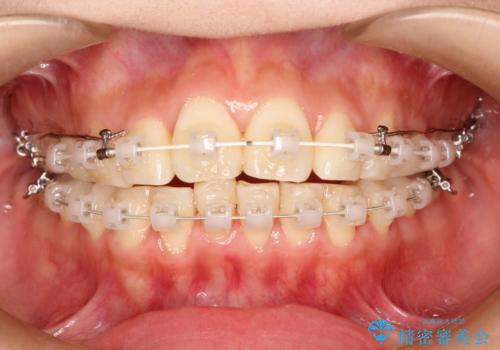

- 上の前歯が出てて、前歯で咬めないとのことで来院されました。

上顎の歯を1本抜歯して、前歯のガタガタと、前方に出ているのを改善する計画としました。

上下の前歯の距離が近くなり、前歯で咬みやすくなり、審美的にも改善できました。